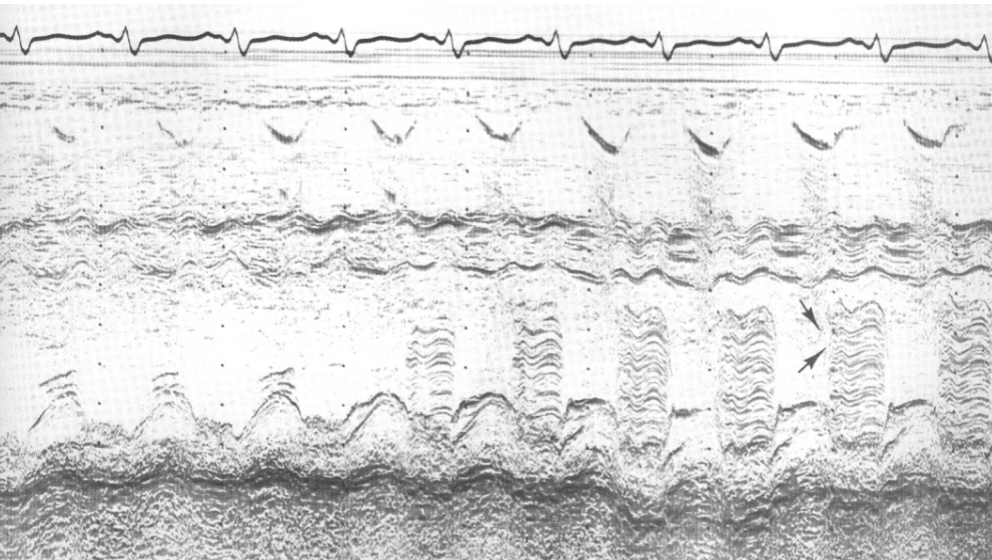

Myxoma m-mode findings:

blunted E-point of MV

reduced E-F slope

can mimic MS

heavy band of echoes behind AMVL in diastole